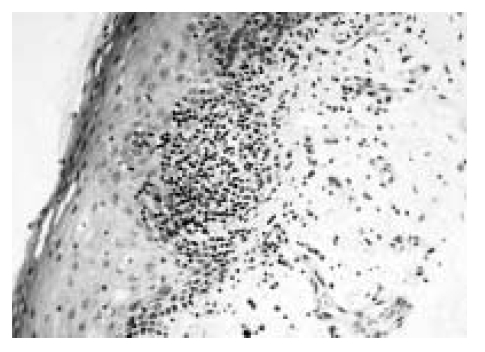

An open lung biopsy was performed at the right lower lobe of the lung. There was dense lymphoplasmacytic infiltration in the interstitium of the lung parenchyme (Figure 5A) and the pleura forming reactive lymphoid follicles with germinal centers (Figure 5B). Multifocal areas of vasculitis (Figure 5C) and interstitial fibrosis were shown without any fibroblastic plug or honeycombing cystic change. The immunohistochemical stains failed to reveal monoclonality of these lymphocytic infiltrations as below; LCA (CD45RB) (+), CD3 (+) and L26 (CD20) (+). In situ hybridization of paraffin block tissue with anti-Ebstein-Barr virus antibody (NCL-EBV-K, Novocastra Lab, UK) was positive.